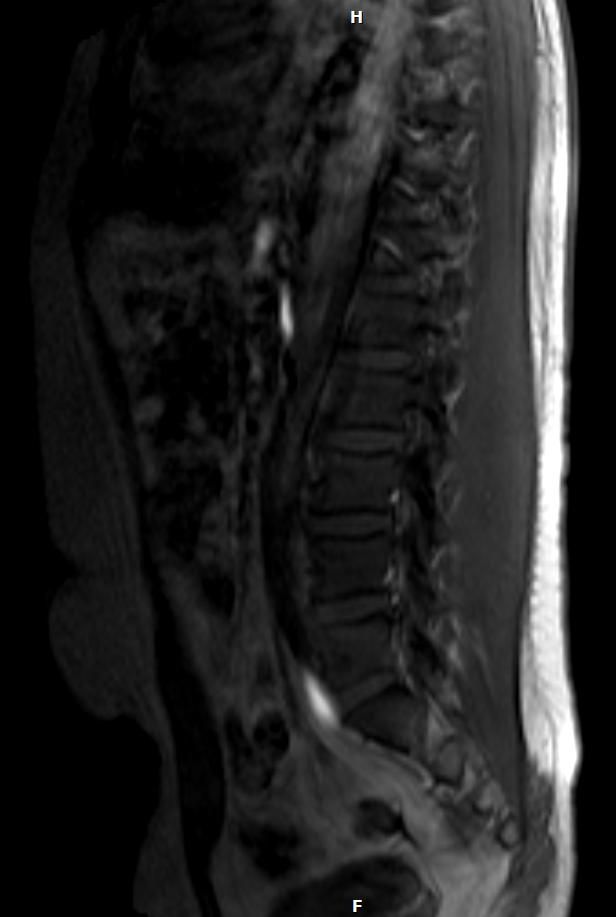

두사진 첫번째 사진이요 딱봐도 하얀색 위에 보이실겁니다.

• 두 장의 MRI 영상을 확인했습니다. 말씀하신 첫 번째 사진의 상부 흉추 레벨, 척추 앞쪽(전방)에 위치한 밝은 고신호 음영이 보입니다.

먼저 결론부터 말씀드리면, 이 음영 하나만 보고 암이라고 단정할 수 없고, 오히려 양성 원인일 가능성이 더 많습니다. 다만 정확한 판단을 위해 몇 가지 중요한 맥락이 필요합니다.

MRI에서 하얗게 보이는 음영, 즉 고신호 병변이 척추 전방에 위치할 때 감별해야 할 원인들은 다음과 같습니다. 가장 흔한 것은 혈관 기형이나 혈관종(Hemangioma)으로, 이 경우 T2 강조 영상에서 밝게 보이고 완전히 양성이며 치료가 필요하지 않은 경우가 대부분입니다. 두 번째로 대동맥이나 주변 혈관의 단면이 특정 시퀀스에서 밝게 보일 수 있습니다. 세 번째로 식도 주변 구조물이나 림프절이 특정 조건에서 고신호로 보일 수 있고, 네 번째로 낭종(Cyst) 류도 T2에서 밝게 보입니다. 악성 병변의 경우 일반적으로 경계가 불규칙하고 주변 조직을 침범하는 양상을 보이는데, 제가 보이는 영상에서는 비교적 경계가 있어 보입니다.

판독의가 "골절은 아니다"라고 했다는 것은 뼈 자체의 문제는 아니라는 의미이고, 담당 의사가 의심스러웠다면 그 자리에서 바로 추가 검사를 권유했을 것입니다. 그러나 판독의에게 "다시 한번 물어보고 오겠다"고 한 뒤 골절 여부만 확인하고 마무리된 것은 다소 아쉬운 상황입니다.

제가 드리고 싶은 말씀은, 이 음영이 정확히 무엇인지는 MRI 전체 시퀀스(T1, T2, 조영증강 여부 등)와 두께, 위치, 경계를 종합해서 판단해야 하므로 지금 제가 드릴 수 있는 답변의 한계가 분명히 있습니다. 다음 외래 때 담당 의사에게 "저 음영이 정확히 어떤 구조물인지, 추가 확인이 필요한지" 직접적으로 질문하시는 것을 강력히 권합니다. 불안하시다면 영상의학과 전문의에게 정식 판독 소견서를 받으시는 것도 방법입니다. 걱정되는 마음은 충분히 이해되지만, 지금 보이는 소견 하나만으로 암을 걱정하실 단계는 아닙니다.